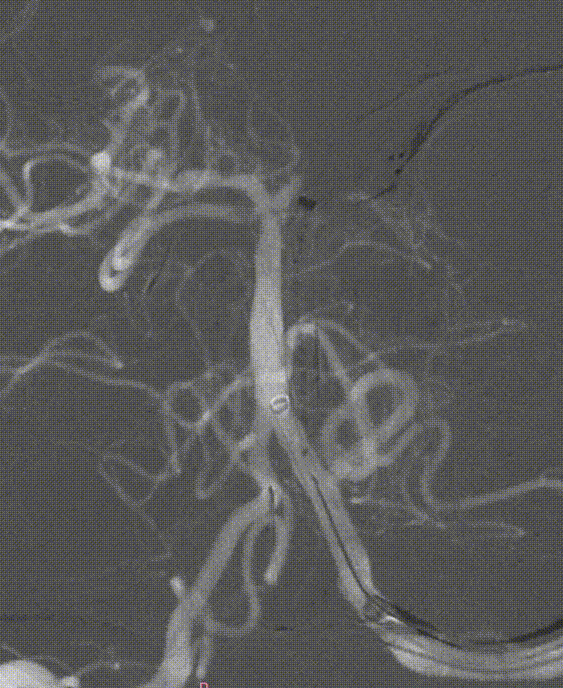

负压抽吸2次,基底动脉顶端部分再通,见栓子向双侧大脑后动脉逃逸。

微导丝携带微导管至右侧大脑后动脉P3段,抽拉结合取栓一次见右侧大脑后动脉再通。

微导丝携带微导管至左侧大脑后动脉P3段,抽拉结合取栓一次见左侧大脑后动脉再通。